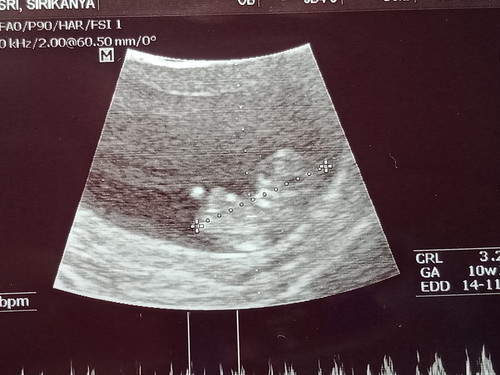

ท้องแรกค่ะ วันนี้ซาวครั้งแรกเห็นเจ้าตัวน้อยดิ้นในท้องเราแล้วอดยิ้มไม่ได้เลย 10w1d ? กำหนดคลอด 14 พฤศจิกา